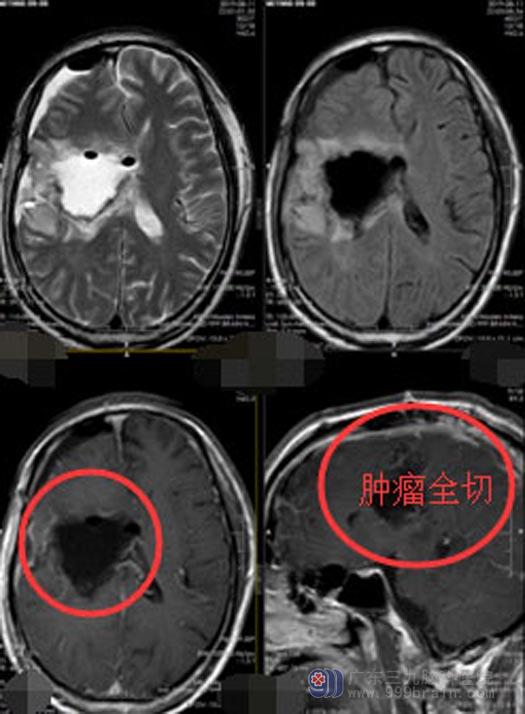

完善术前准备后,由鲁明副院长主刀行“右额颞岛叶、丘脑基底节及胼胝体体部巨大复发胶质瘤切除术”,术中导航定位,显微镜下分块将肿瘤切除,术后李叔言语功能正常,说话流利,左侧肢体肌力同术前。

▲手术后